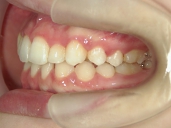

矯正歯科 治療後 左

矯正歯科 治療後 右